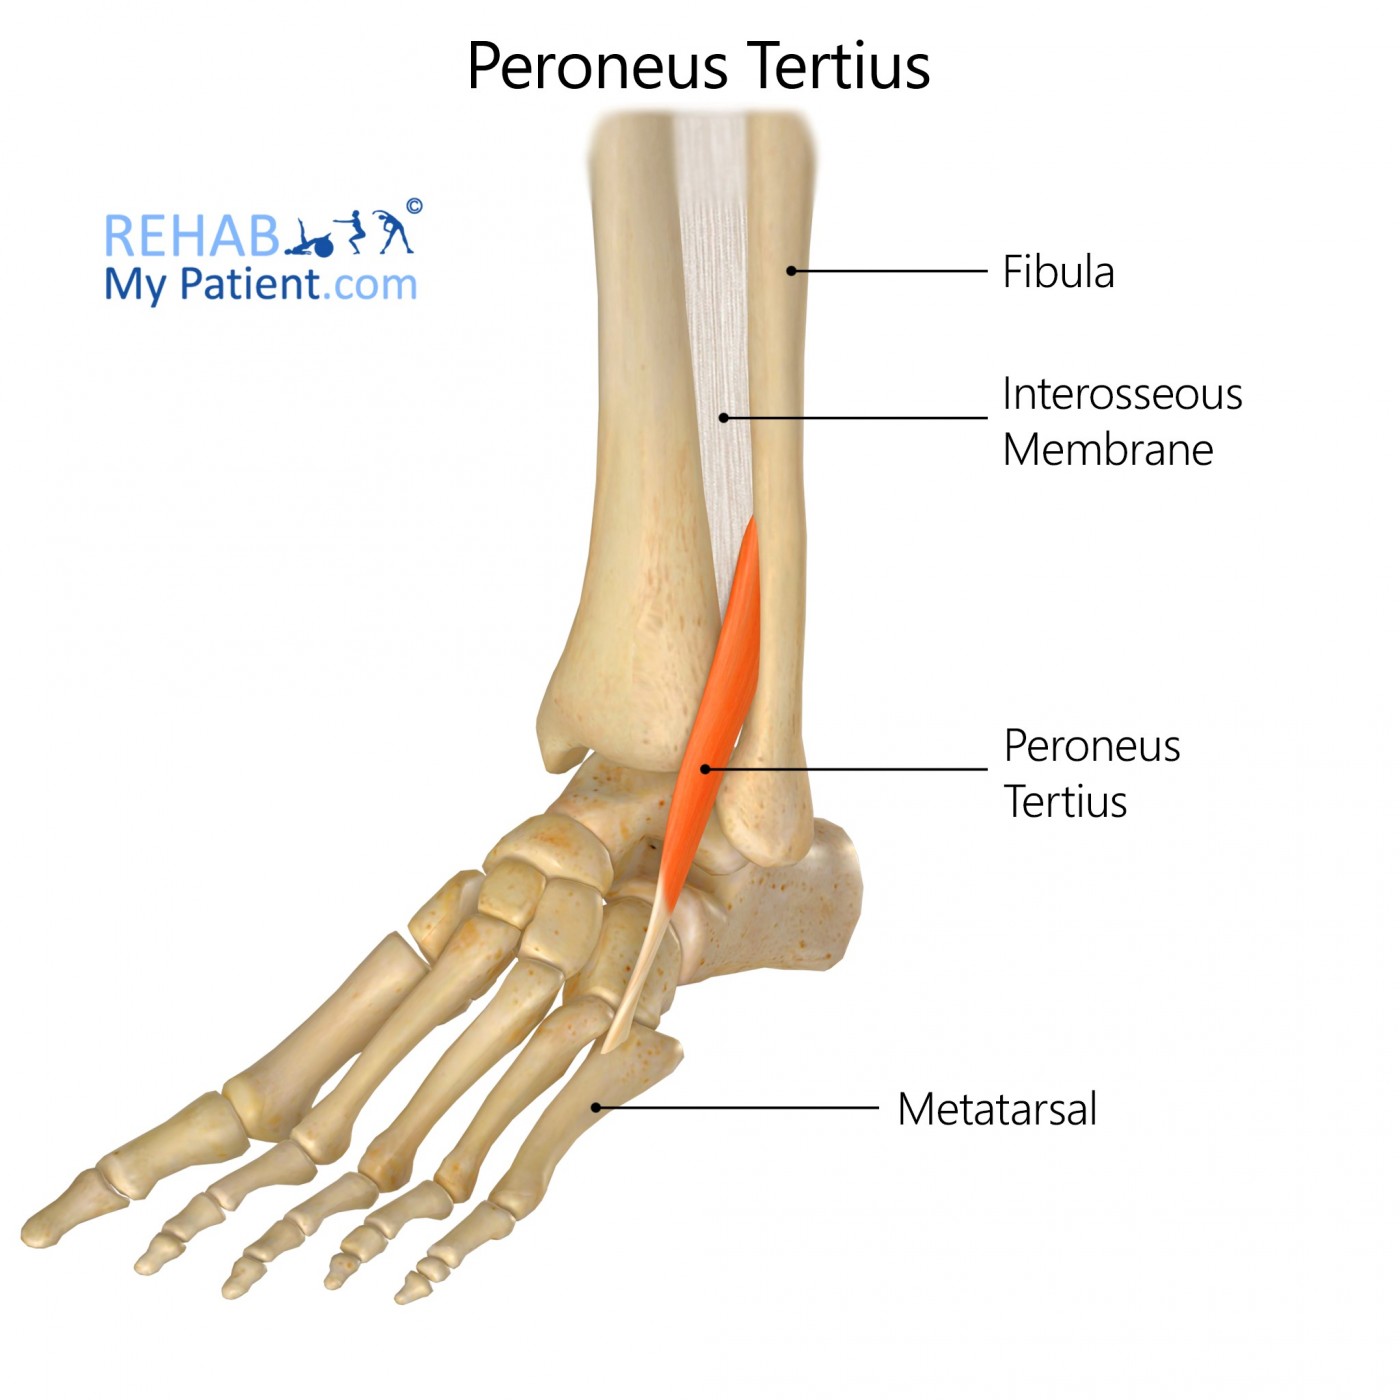

what does the peroneus Tertius look like?

peroneus Tertius

O: distal 1/3 of fibula

I: dorsal aspect of base of 5th metatarsal

A: dorsiflexion and eversion

N: deep peroneal

peroneus Tertius origin?

distal 1/3 of fibula